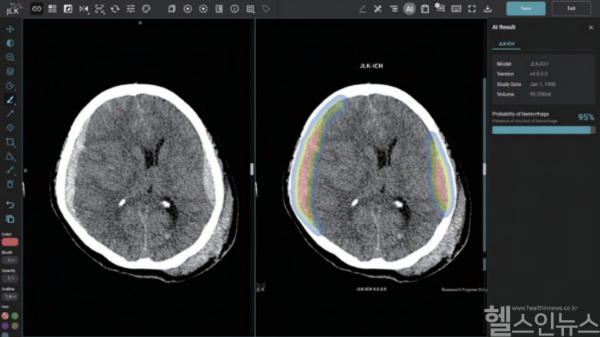

JLK-ICH는 임상연구를 통해 발생 패턴이 다른 5가지 뇌출혈 유형에 대해 높은 검출 성능을 입증했다. 특히 뇌출혈은 혈관이 막히는 뇌경색보다 중증도가 높아 신속한 진단과 치료가 환자 예후에 결정적이다. 회사는 이번 솔루션이 시간 단축을 통해 골든타임 확보에 기여할 것으로 기대한다고 설명했다.